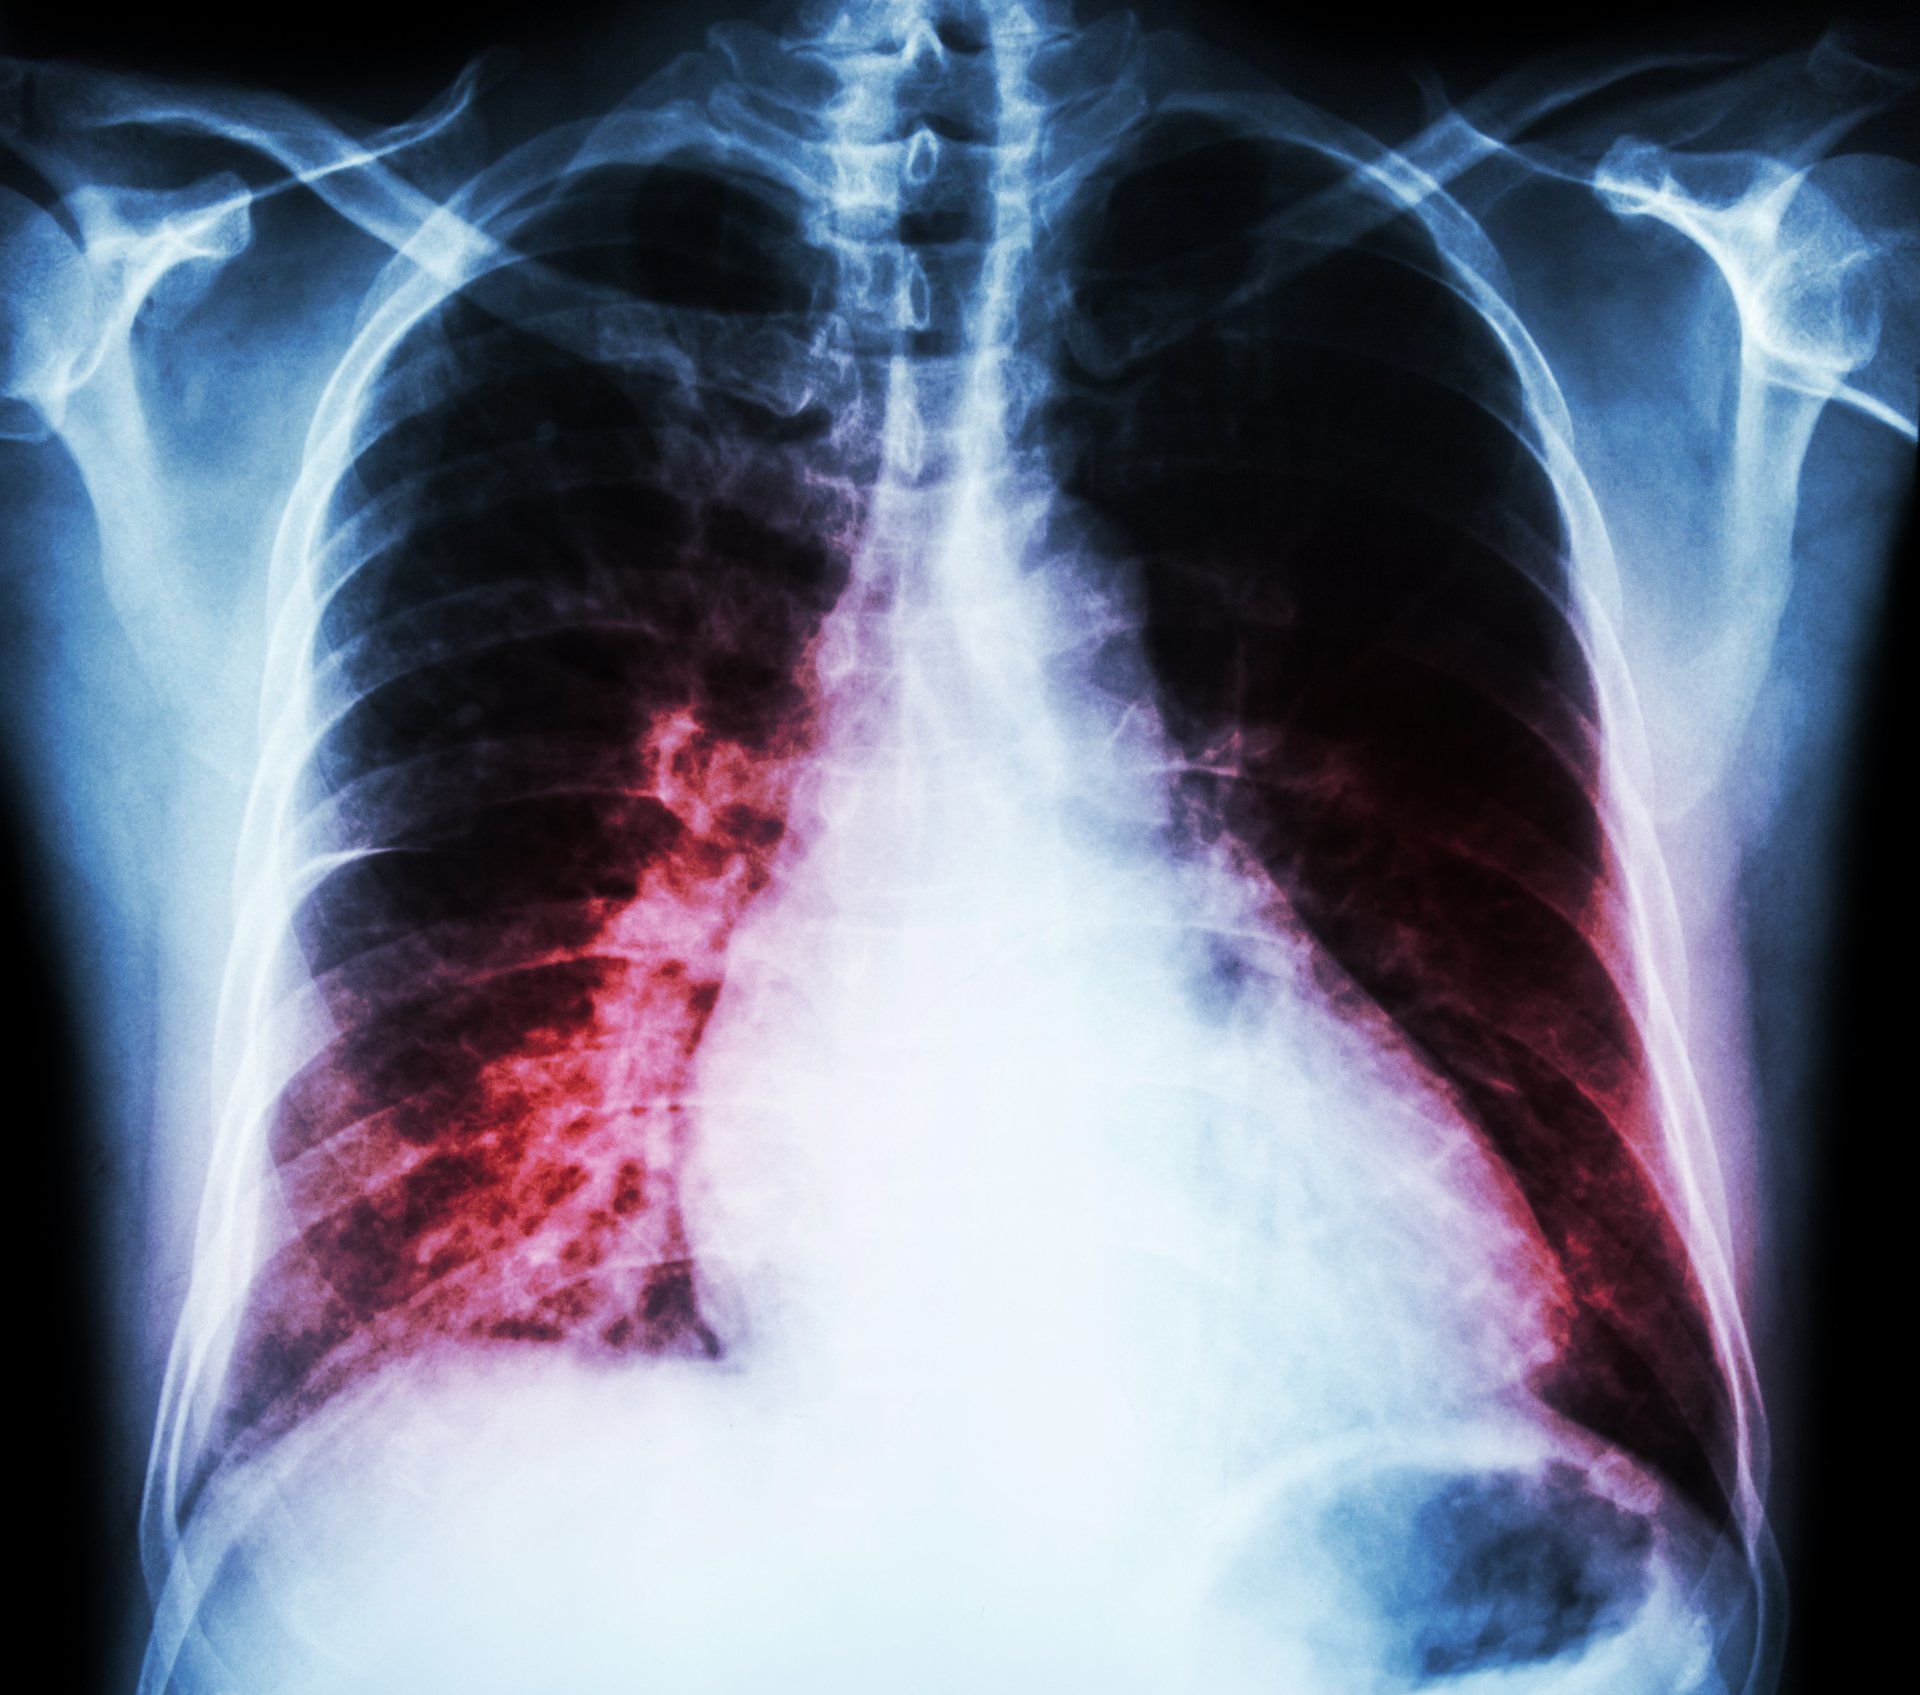

Bei Symptomen wie Atemnot, Beinschwellung sowie reduzierte Belastbarkeit, sollte mit entsprechenden Untersuchungen (EKG, Echokardiographie und Labor) an das Vorliegen einer Herzinsuffizienz gedacht, gesucht und ihre Genese eruiert werden.